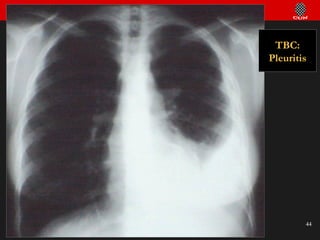

Infección pulmonar tuberculosa Reinfección: Formas de presentación Neumonía cavitada Linfadenitis Pleuritis Diseminación bronquial Diseminación hematógena (Miliar) Fistulizaciones Afectación de otras vísceras

TBC: Pleuritis